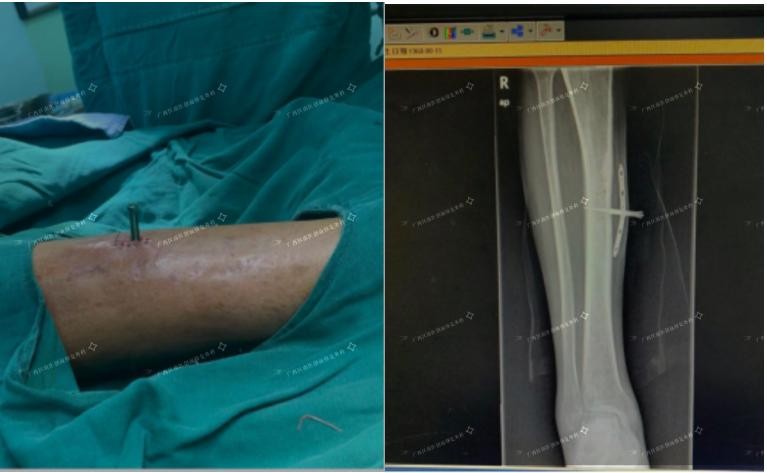

骨膜牵张术应用于治疗下肢动脉闭塞缺血患者